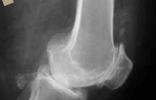

정상 관절은 각 뼈의 끝에 연골이 있어 뼈끼리 부딪치는 것을 방지하는 쿠션 역할을 하면서 관절의 운동을 부드럽게 해줍니다. 골관절염의 원인은 이런 중요한 역할을 하는 연골이 손상되어 닳아 없어지고 그 밑에 있는 뼈에도 손상이 오며 기형적으로 뼈가 자라나면서 관절의 통증, 변형 및 운동 장애를 일으킵니다.

주로 관절을 많이 사용한 후, 즉 저녁 시간이나 잠자기 전에 통증을 호소하며, 아침에 일어나면 관절이 뻣뻣하나 관절을 움직이면 보통 30분 이내에 좋아집니다. 관절을 움직일 때 연골과 뼈가 부딪히는 ‘뻐적뻐적’소리가 나고 관절을 움직이면서 손으로 만져 보면 무엇인가 탁탁하면서 만져지는 느낌이 듭니다. 이런 병변이 진행되면 뼈에 변형이 오고, 관절을 움직일 수 있는 운동 범위가 제한되고, 결국에는 관절을 전혀 움직이지 못하기까지 이릅니다. 주로 침범하는 관절로는 체중의 부하를 많이 받거나 많이 사용하게 되는 무릎관절, 고관절, 척추관절, 그리고 손관절입니다.